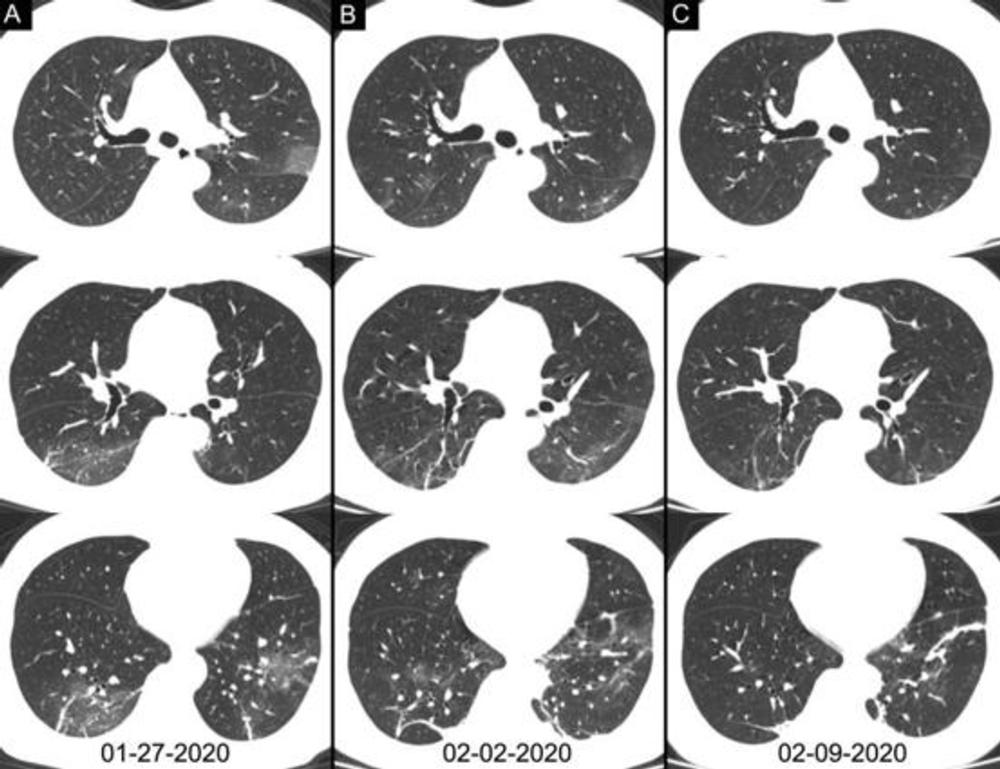

Figure 4. Chest CT images of a 46-year-old woman with fever for 4 days. The result of RT-PCR assay for the SARS-CoV-2 using a swab sample was positive on February 4, 2020 and was negative on February 12. Three chest CT scans obtained from (A) January 27, (B) February 2 and (C) February 09, 2020 show the gradual absorption of bilateral ground-glass opacities and linear consolidation.